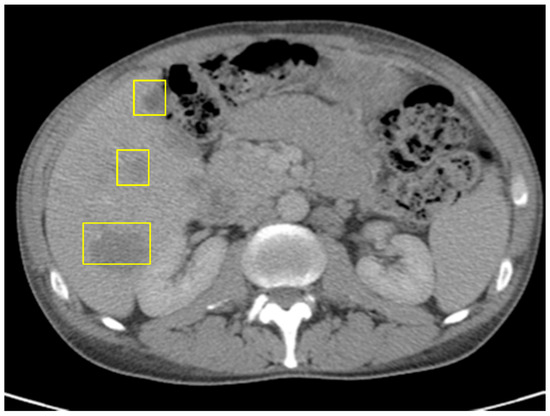

Given the tumor’s POLE mutation, high TMB, and refractory response to cytotoxic therapy, the patient was considered for immunotherapy. He was initially started on single-agent pembrolizumab, an anti-PD-1 monoclonal antibody. Although his CEA and ctDNA levels rose during the initial treatment, pseudoprogression was suspected. Due to the patient’s preference and clinical suspicion of delayed immunologic response, therapy was escalated to combination immune checkpoint blockade with nivolumab (anti–PD-1) and ipilimumab (anti–CTLA-4). After two cycles, follow-up CT demonstrated further enlargement of hepatic lesions and persistent splenomegaly (Figure 5), along with a CEA increase to 183.4.

Figure 5. CT of abdomen/pelvis right after Pembrolizumumab: slight decrease in size of hepatic masses, stable retroperitoneal lymph nodes, and small splenomegaly.